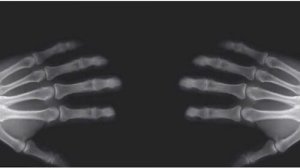

Stawy to miejsca, w których stykają się kości i ruchomo ze sobą łączą. Powierzchnie stawowe kości pokryte są chrząstką szklistą i chronione są przez torebkę stawową, w której znajduje się maź stawowa. To wszystko minimalizuje tarcie i ułatwia płynny ruch kości względem siebie.

Strzelanie palcami ma swój początek w mazi stawowej. Podczas rozciągania palców w niej właśnie tworzą się pęcherzyki powietrza i wypełniają one wolne przestrzenie torebki stawowej.

Przy użyciu odrobiny siły, pęcherzyki powietrza ulegają rozbiciu i wydobywa się charakterystyczny dźwięk strzelania.